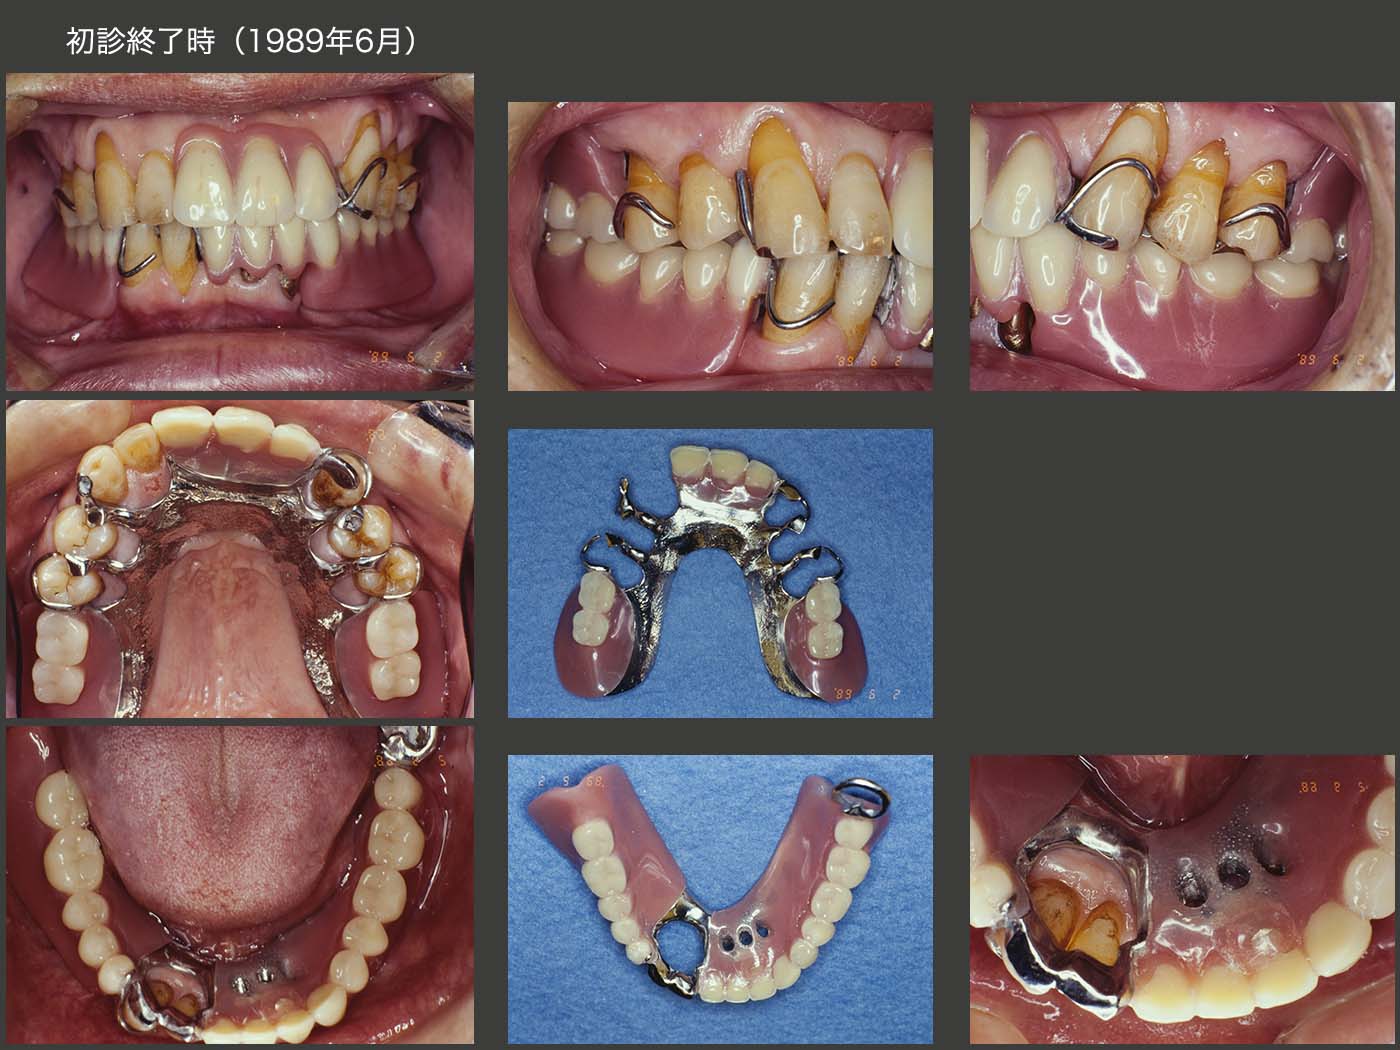

1989年6月,初診終了時の状態.左下2の近心に6mmの歯周ポケットが存在したが,ここ以外は5mm以内に収まった.アタッチメントはBona 604Aを用いた.なお,根面板を連結固定してアタッチメントを付与した症例は,後にも先にもこのケース1例だけである.

初診終了時の義歯を装着した状態.左下の根面アタッチメントの支台歯辺縁歯肉を開放し,唾液による自浄性の向上を図った.

さて,ここで大変なミスを犯してしまった.それは,右下2および3に切端レストを付与してしまったことである.すなわちこの分,咬合が挙上してしまった.(言い訳になるが,右上3,4間が空いていることから,右下3の突き上げで,右上3がフレアーアウトしたと考えれば,咬合が少し低くなっていたとも考えられる.そこで切端レスト分咬合を高くしたという屁理屈も成り立つ.しかし,長い年月をかけて徐々に下がった咬合を昔に戻してはいけないと今は考えている.)咬合を挙上すると,一般的には咬合力が強くなってしまう傾向がある.特に咬合力が元々強い人の咬合を挙上してしまうことは,さらに咬合力が増してしまうので大変危険である.